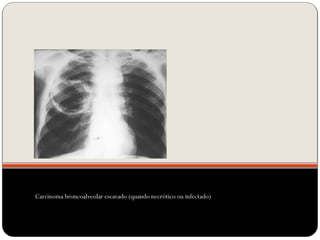

Carcinoma broncoalveolar escavado (quando necrótico ou infectado)

Carcinoma broncoalveolar escavado(quando necrótico ou infectado)